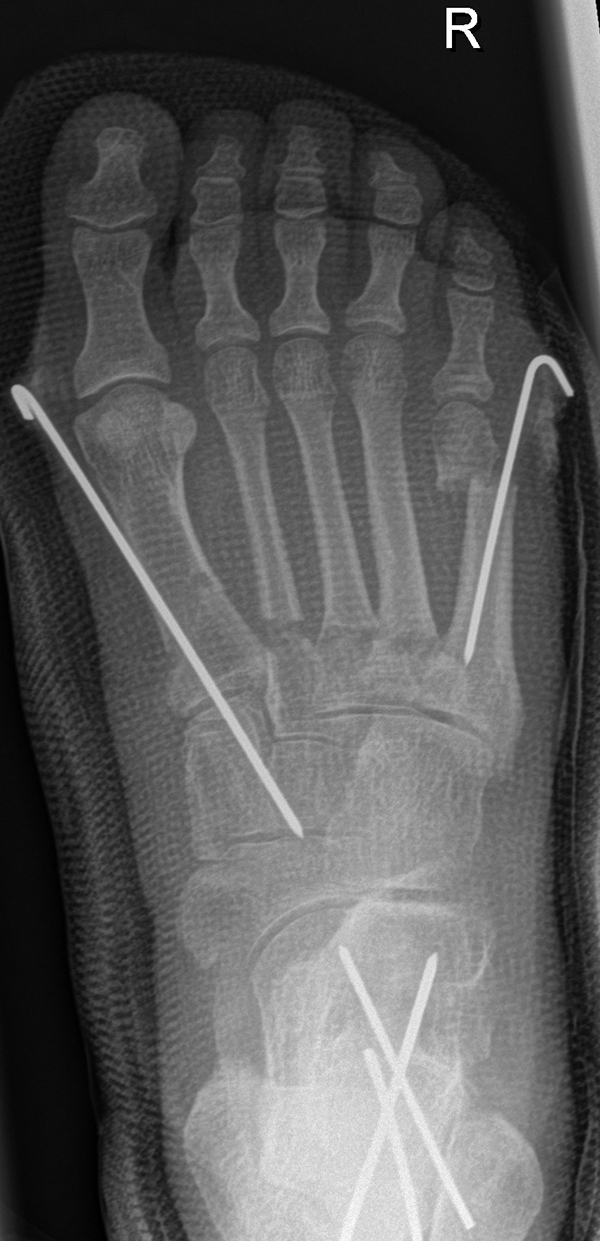

Zusätzlich schränken Wachstumsfugen die Wahl der Osteosynthese ein. Eine die Fuge kreuzende Osteosynthese ist ausschließlich mit Kirschner-Drähten möglich (Abb. 3).

Abb. 3 a-j: Beispiel einer Calcaneusverschiebeosteotomie mit offenen Wachstumsfugen und der entsprechenden Osteosynthese mit Kirschner Drähten. Lokalisation der Osteotomie (a), Lage der Fräse (b-d), Drahtlage mehrere Ansichten (e-h), Heilung der Osteotomie 4 Wochen postoperativ und Entfernung der Drähte (i-j).

Zum Lesen der Bildbeschreibung und zur Vollansicht bitte die Bilder anklicken. Bilder: A. Helmers.